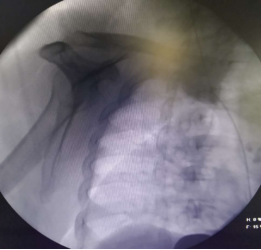

血液净化中心医生制定了内瘘结扎方案,把人为建立血流回心的“高速公路”封堵,DSA引导下穿刺上腔静脉置入一根23cm的长期透析导管,手术难度很大。

DSA下行血管造影+上腔静脉穿刺+置入长期透析导管手术过程(白色粗箭头所指用经皮血管穿刺套件进行上腔静脉穿刺过程)